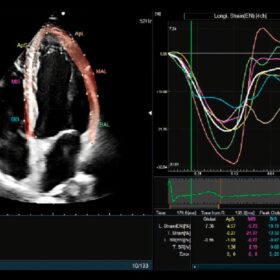

Cardio 2D and Color mode

- Great image quality delivered by our latest processing technologies like eFocusing and Carving Imaging.

- Premium, AI-based measurement functions that take patient diagnosis to the next level.

Choose the ARIETTA 750 and you get high image quality delivered with a choice of different options. But perhaps most importantly, the ARIETTA 750 puts you firmly in charge of your patients’ diagnostic data through advanced measurement technology – including criteria and indices for various organ functions.

The result: diagnose pathologies at the touch of a button, more efficiently than ever before.

- Advanced cardiac reporting workstation